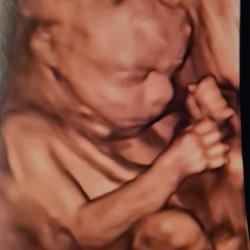

Hier een baby van 2kg300 op 32 weken, maar er was geen sprake van inleiden of enig probleem.. gewoon een stevige baby op komst 😊